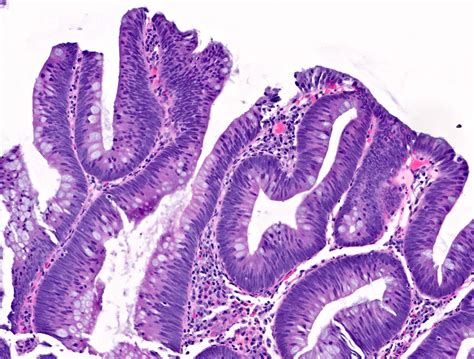

What is a Tubular Adenoma of the Colon?

A tubular adenoma is a type of polyp that forms on the inner lining of the colon. These polyps are composed of glandular tissue and are characterized by their tubular shape. Tubular adenomas are the most common type of adenomatous polyps, which are known to have the potential to become malignant if left untreated. Early detection and removal of these polyps are essential for preventing the development of colorectal cancer.